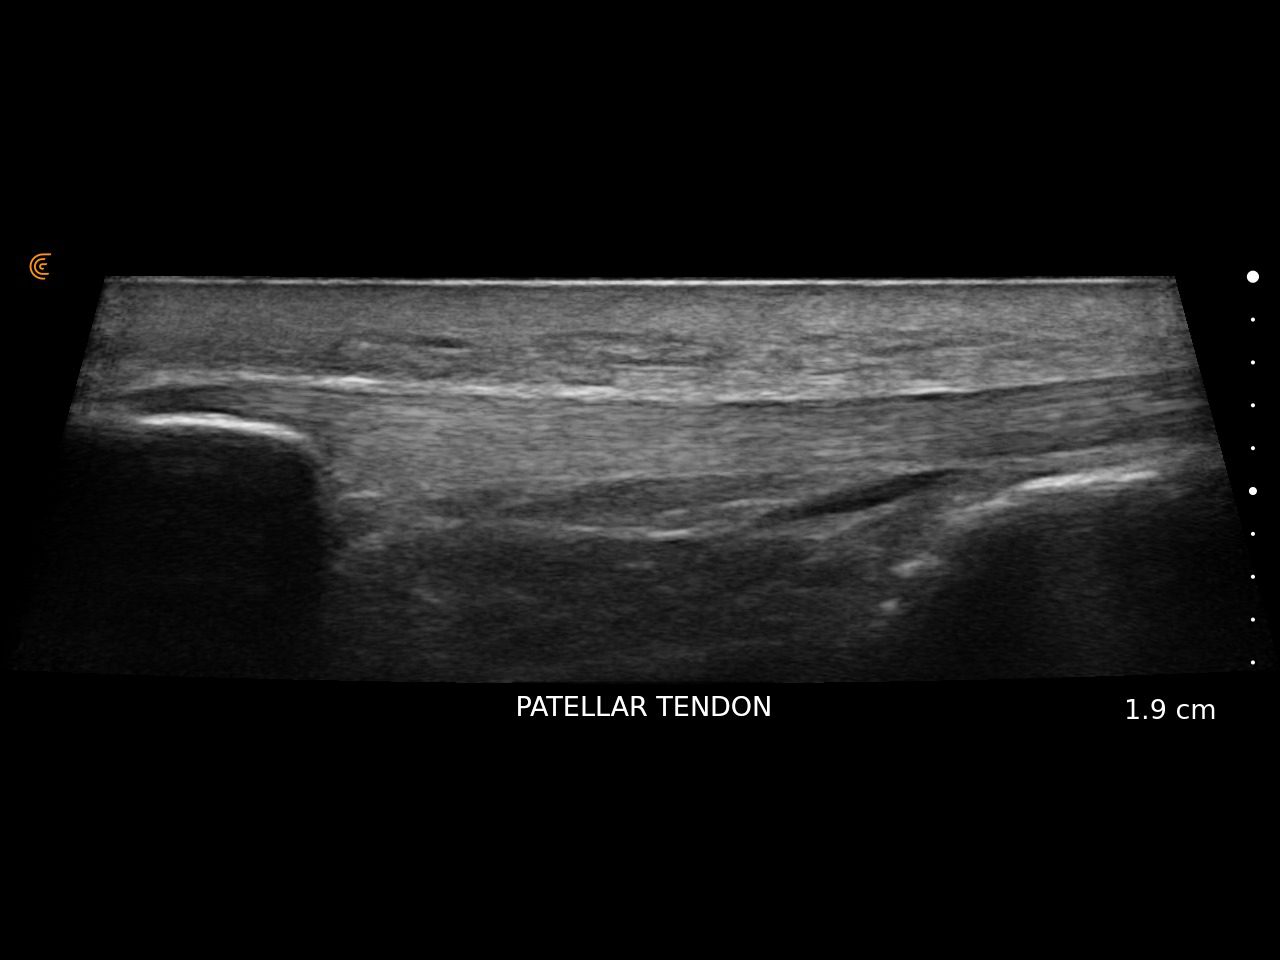

Specialized presets and high resolution provide fast, accurate imaging for athletes’ needs.

Use real-time imaging to assess injuries, monitor recovery, and tailor treatment plans—delivering better outcomes for every patient.